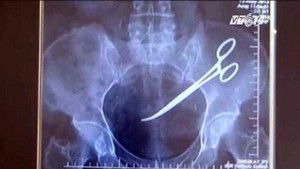

Bác sĩ Trần Văn Phúc (Bệnh viện Đa khoa Saint Paul, Hà Nội) cho biết, chuyện một chiếc kéo phẫu thuật nằm trong bụng bệnh nhân tới chục năm mà bệnh nhân không có cảm giác đau đớn là chuyện bình thường.

Do một tai nạn, ông Ma Văn Nhật đến khám tại bệnh viện thì phát hiện trong bụng có một chiếc kéo dài 15cm do bác sỹ quên khi phẫu thuật năm 1998.